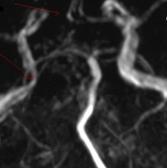

ARM arata la nivelul vaselor precerebrale:

stenoza strānsa la nivelul ACI stāngi

stenoza larga la nivelul ACI drepte

absenta AV stāngi.

Intracranian, ARM evidentiaza:

leziuni ATS multiple

absenta A1 dr

hipoplazia P1 bilateral